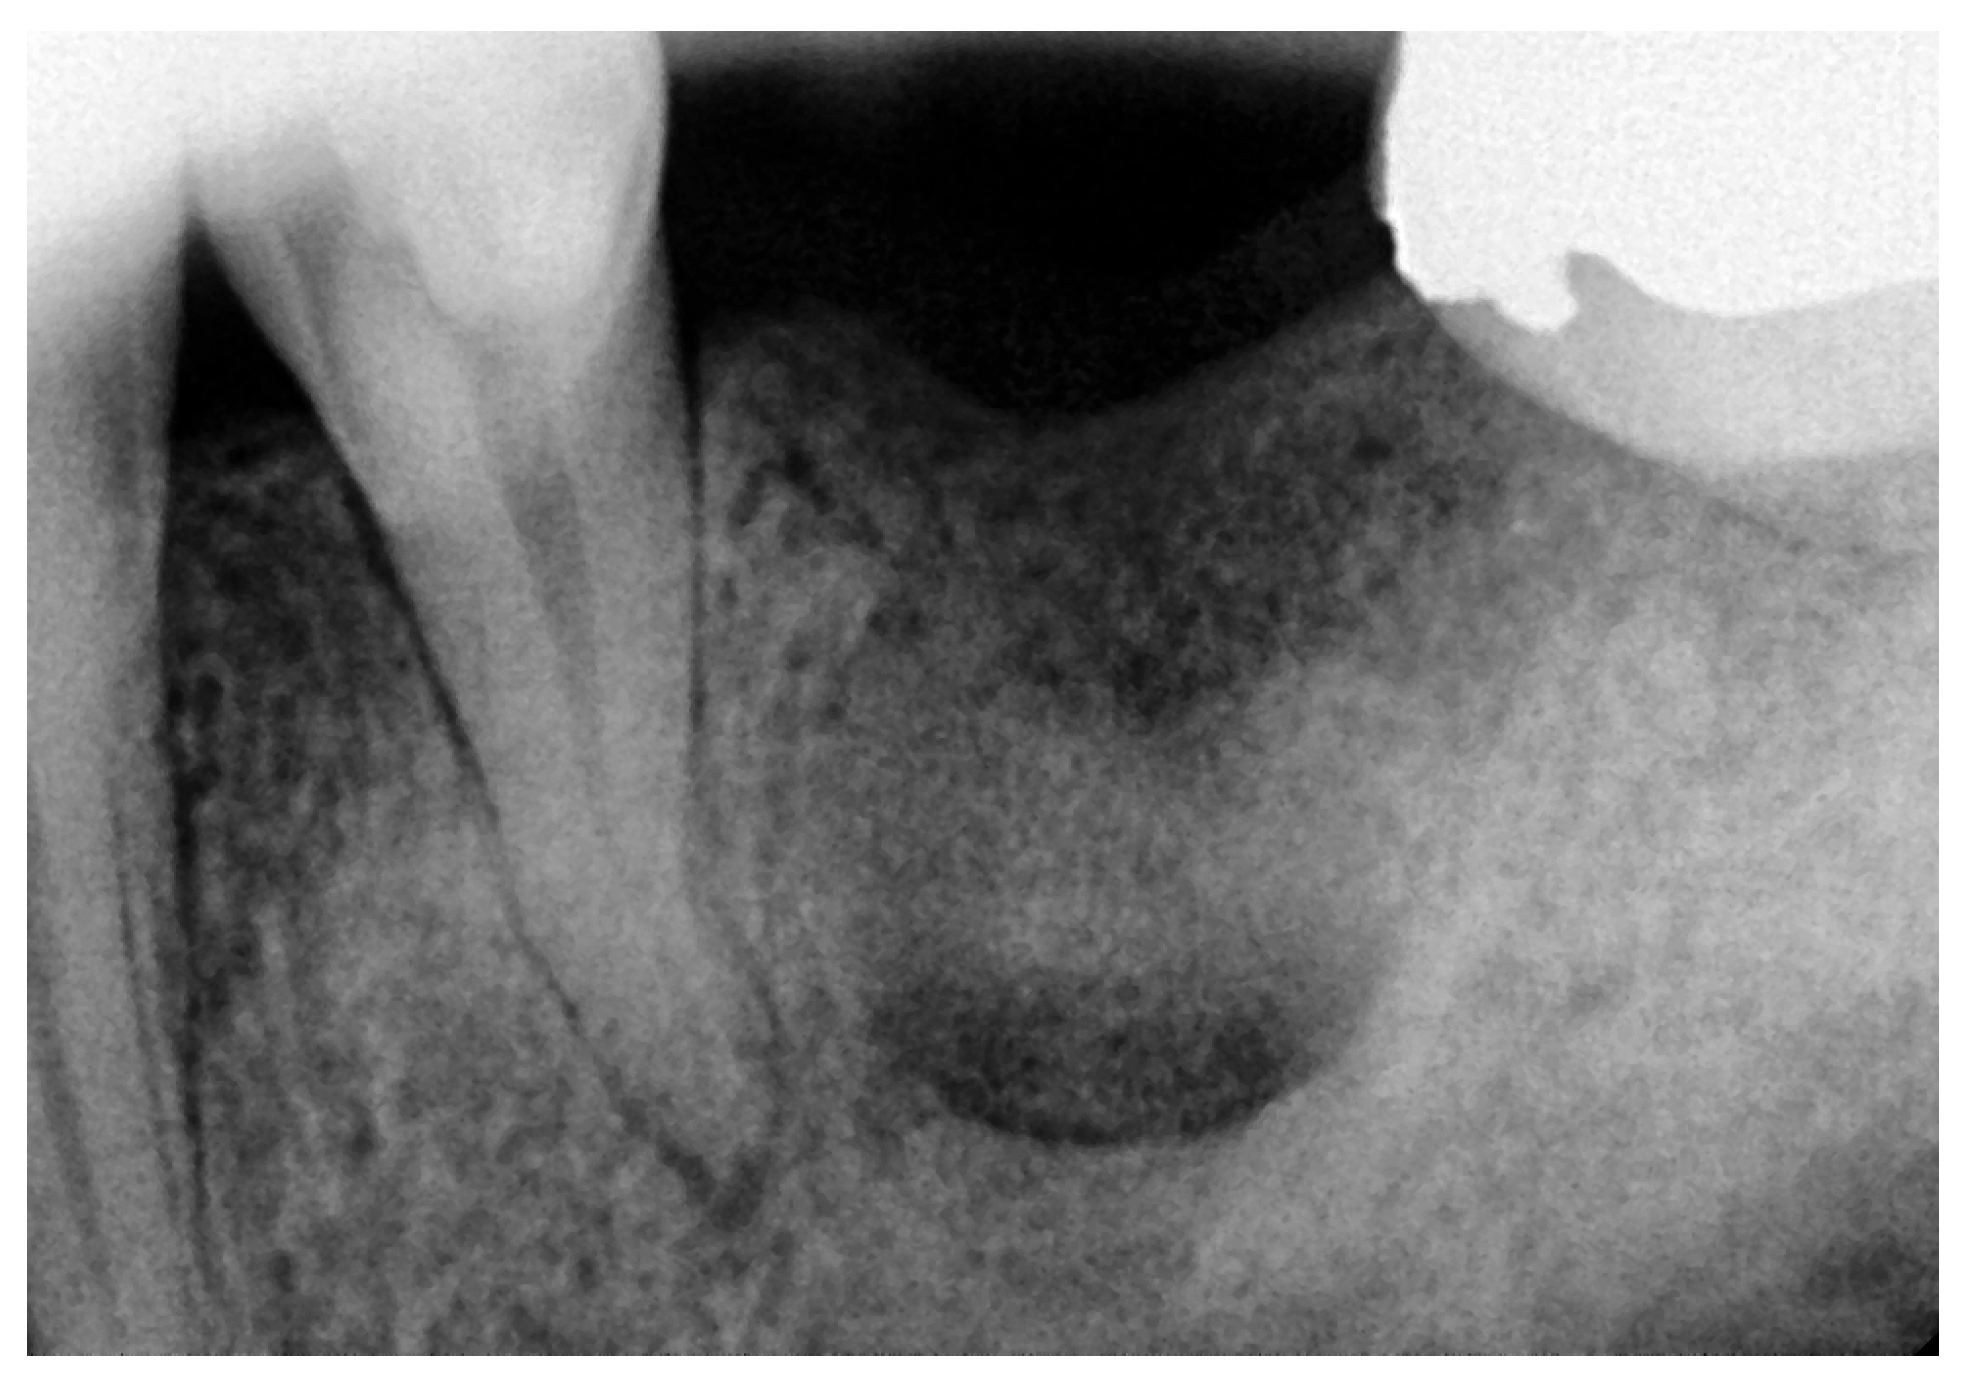

2.1. Initial Visit, Radiographic Evaluation and Diagnosis